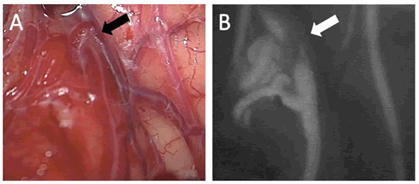

On day three, suboccipital craniotomy was performed and microscopic observation revealed a small nidus on the left caudal surface of the cerebellum. The cerebellar haematoma was evacuated for decompression and to enable better viewing for the AVM excision. Closer inspection showed one of the veins draining from nidus as a ‘red vein’ (Figure 2A). Intravenous indocyanine green injection revealed a 4 ml nidus but with no early draining veins (Figure 2B).

The nidus was safely removed, and gross total excision confirmed with repeat indocyanine green injection. The AVM cavity was connected to the haematoma cavity, which implied that the origin of bleeding was the AVM as opposed to PICA dissection and no further exploration of PICA was considered intra-operatively.